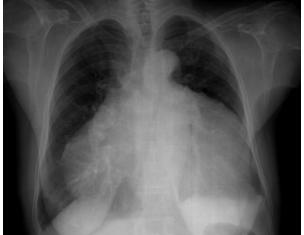

Figure 9: X-ray chest PA (postero-anterior) view showing right-sided pleural effusion and endocardial calcification over the left ventricle in burn- out stage of EMF (endomyocardial fibrosis).

Endocardial calcific deposits can be present involving diffuse areas of the ventricles and Cockshott et al described this feature in 1967. Calcification, an impressive finding on imaging denotes a burnt-out phase of endomyocardial fibrosis (EMF) and confirming the malignant nature of the disease. Chest X-rays show varying degrees of cardiomegaly and at times typical endocardial calcifications in the left and right ventricles as shown in Figure 9 (left ventricular endocardialcalcification) [24- Figure 2(a)] and in Figure 16 (right ventricular endocardial calcification)[25- Figure 2 (c)- shows calcification in both ventricles], [26].

A large pericardial effusion is often present and noted as another peculiar feature of this disease [27]. Pericardial effusion and ascites dominate the clinical picture of right ventricular EMF [28], [29], [30]. Etiology of pericardial effusion is possibly inflammatory and EMF is to be considered as ‘pancarditis’ since all the layers are involved. Adhesions between the parietal and visceral layers of the pericardial sac may develop and visible as strong fibrotic strands as shown in Figures 29. A right ventricular EMF presented with massive pericardial effusion was detected in a 85 –year old female as shown in Figure 16, 17 and 29[31]. Cardiomegaly can be exaggerated by pericardial effusion, and pleural effusion is also a common finding as shown in Figure 9 [16-Figure 2]. Giant ascites in EMF is not fully explained by congestion alone and it is due to peritoneal inflammation and reduced reabsorption of peritoneal fluid, caused by fibrosis since the fluid is an exudate with predominant lymphocytes. The triad of elevated JVP (Jugular venous pressure), ascites and hepatomegaly formed the hallmark of right ventricular EMF.